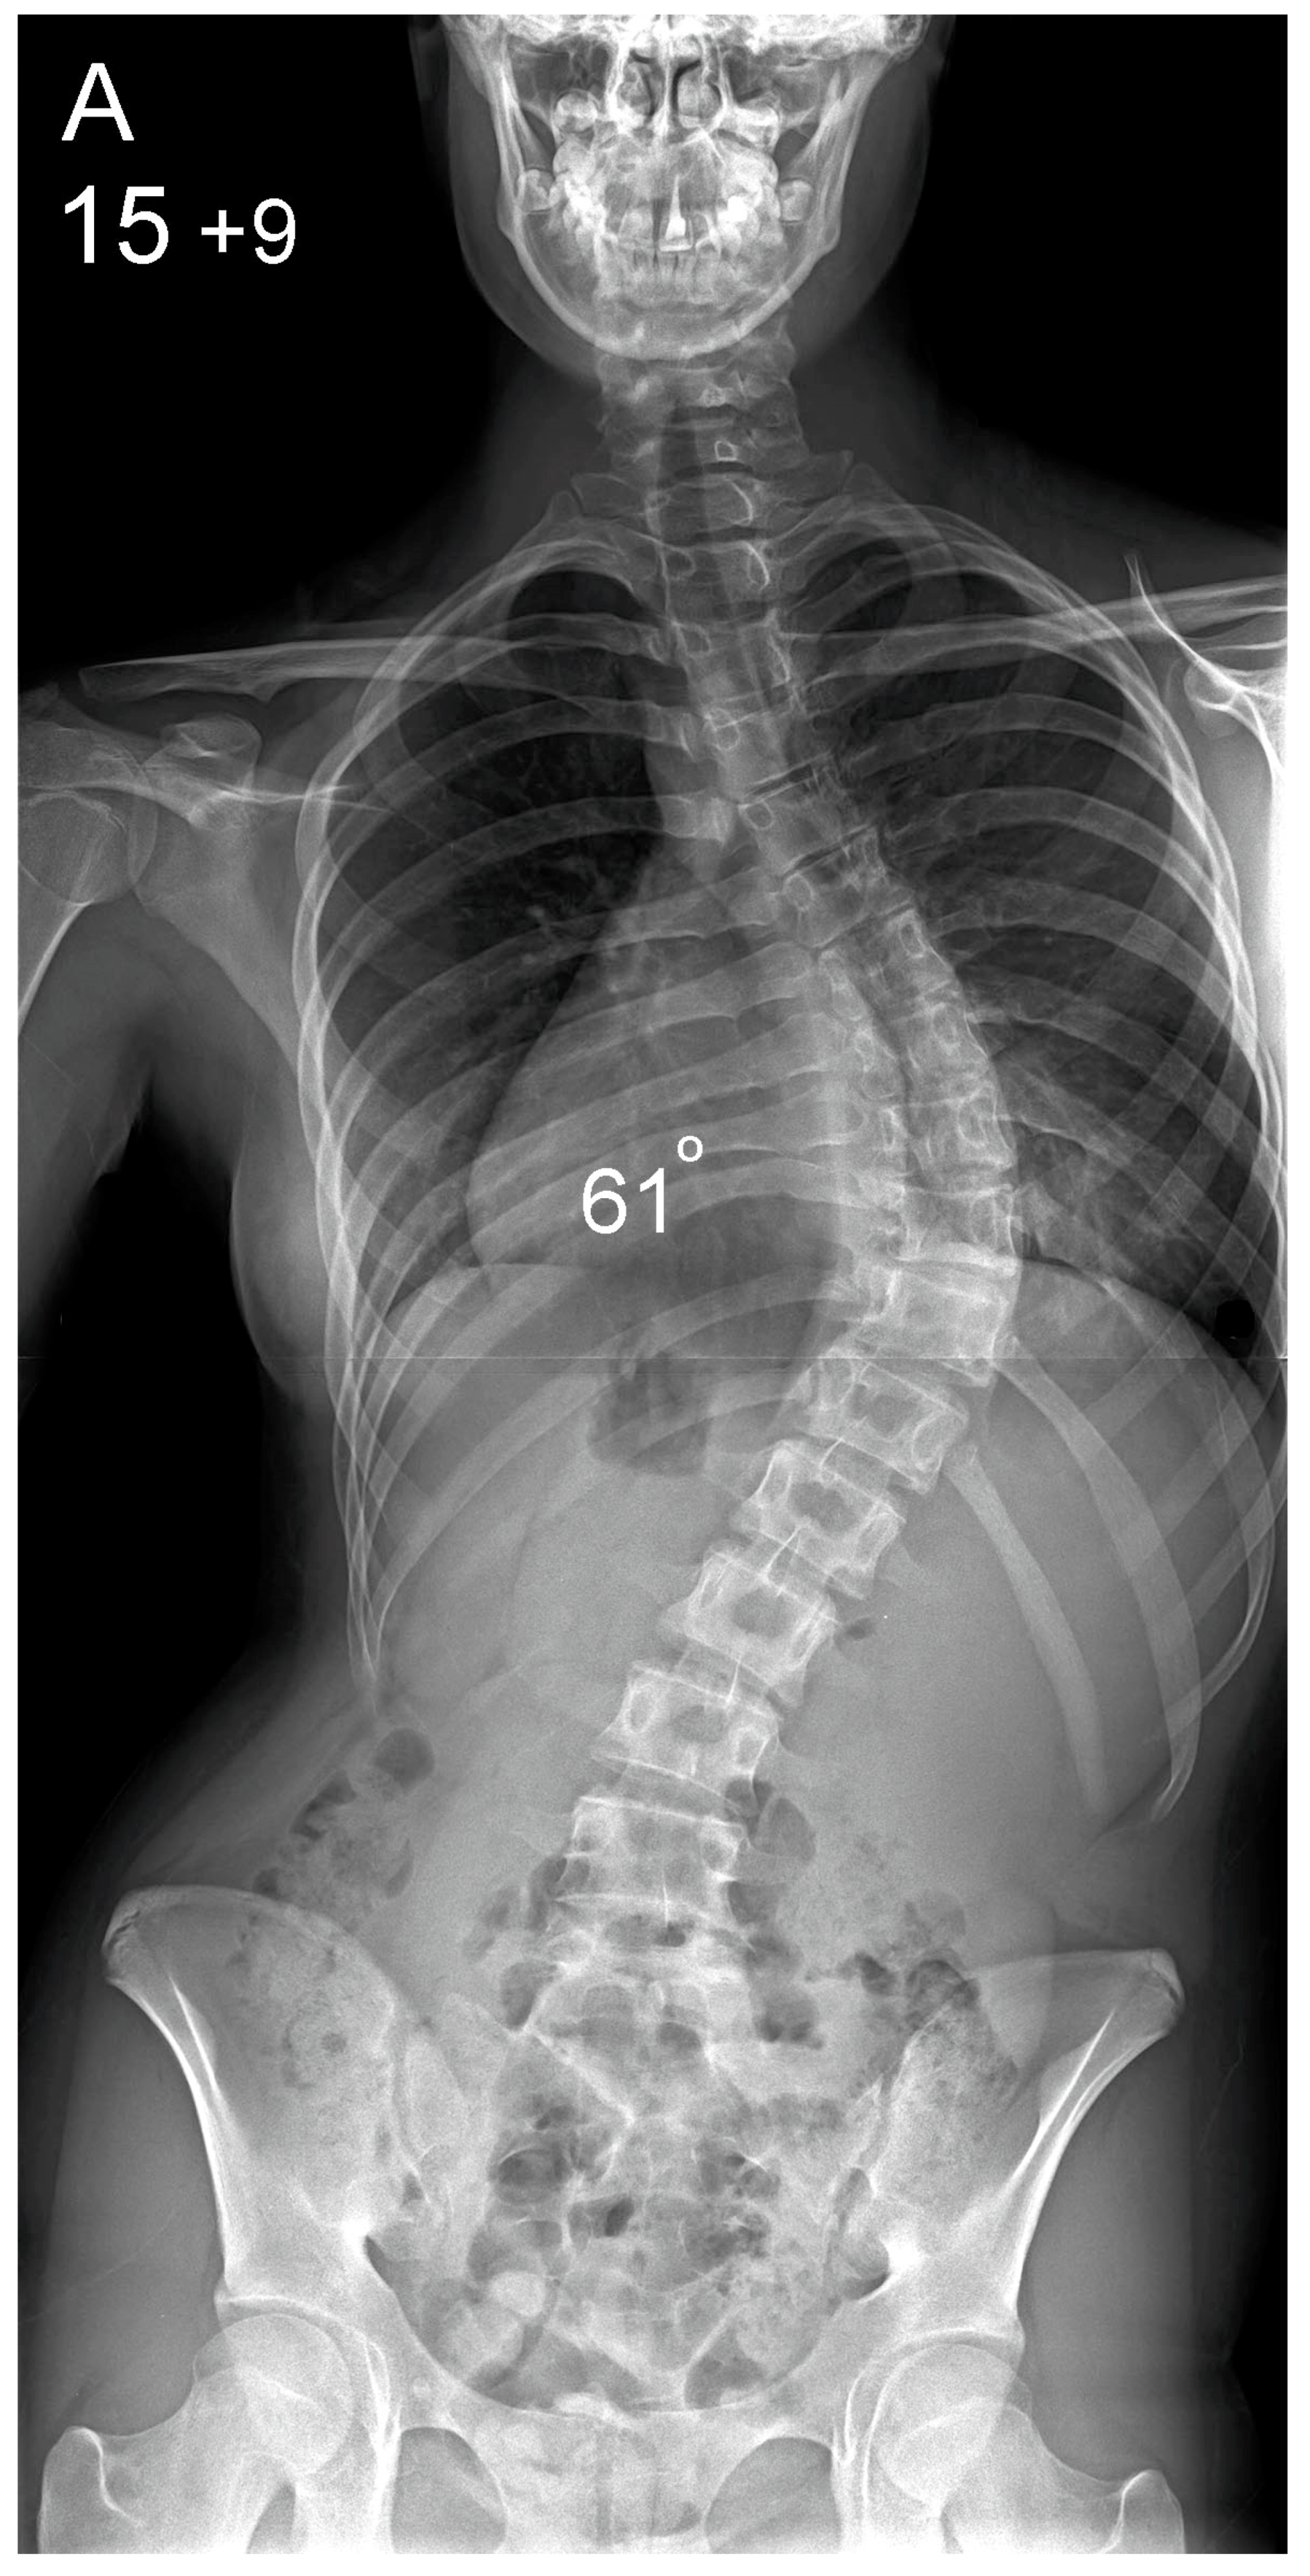

Figure 2.

Patient aged 15 years and 9 months with a right thoracic AIS producing thoracic translocation and listing of the trunk to the right, as well as a lordotic thoracic spine causing spinal penetration into the chest, partial bronchial obstruction and right lower lobe atelectasis (A,B). The patient underwent posterior scoliosis correction using the HS technique which restored segmental and global coronal/sagittal spinal balance at latest follow-up (age 19 years and 2 months) into adult life (C,D). Clinical photographs demonstrate excellent correction of the coronal deformity and associated rib hump after scoliosis surgery (E–H).